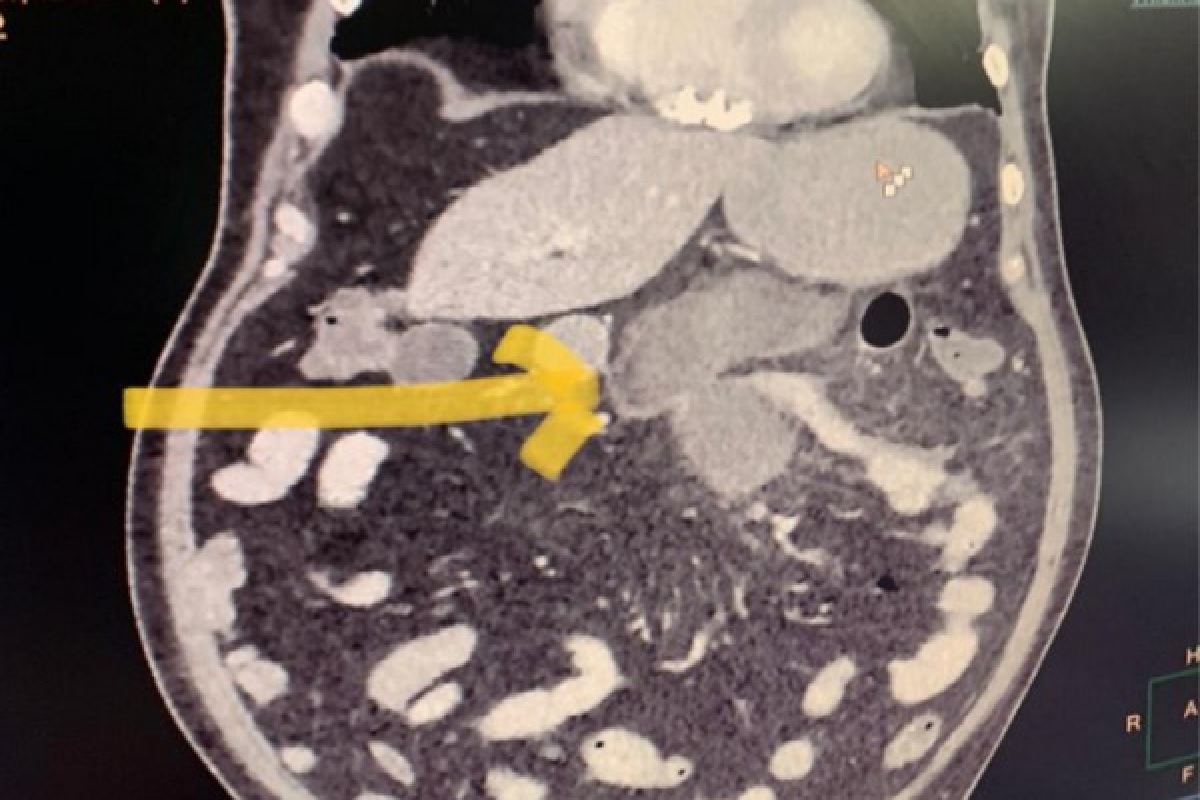

नवी दिल्ली, 22 मे: देश एकीकडे कोरोनासारख्या महामारीचा सामना करत आहेत. तर दुसरीकडे आता म्युकरमायकोसिस (Mucormycosis ) म्हणजेच ब्लॅक फंगस हे नवं संकट उभं ठाकलं आहे. ब्लॅक फंगस **(Black Fungus)**च्या रुग्णांचा आकडा आता दिवसेंदिवस वाढत चालला आहे. दरम्यान आताच समोर आलेल्या माहितीनुसार, दिल्लीतल्या सर गंगा राम रुग्णालयात छोट्या आतड्यां (Small Intestine) ना ब्लॅक फंगस झाल्याची घटना आढळून आली आहे. दिल्लीचे रहिवासी असलेले 56 वर्षीय कुमार यांनी कोरोनामुळे आपली पत्नी आणि कुटुंबियातल्या दोन सदस्यांना गमावलं. कुमार यांनी आपल्या पत्नीसोबत कोरोनाची चाचणी केली होती. तसंच त्यांना कोविड-19 सौम्य लक्षणंही जाणवत होती. त्यांची चाचणी पॉझिटीव्ह आली. पत्नी मृत्यू झाल्यानंतर एक दिवस कुमार यांच्या अचानक ओटीपोटात दुखू लागलं. या पोटदुखीकडे त्यांनी दुर्लक्ष केलं. अॅसिटीडी किंवा तणावामुळे दुखत असेल म्हणून त्यांनी अॅसिटीडीची औषध घेतली. त्यामुळे तीन दिवस उपचारास उशीर झाला आणि त्यांना ब्लॅक फंगसची लागण झाल्याची बाब समोर आली. तीन दिवसानंतर त्यांना सर गंगा राम रुग्णालयातील (Sir Ganga Ram Hospital) कोविड-19 च्या इमरजन्सी वॉर्डमध्ये दाखल करण्यात आलं आहे. रुग्णालयात दाखल केल्यानंतर त्यांच्या पोटाचा सीटी स्कॅन करण्यात आला. त्यावेळी रिपोर्टमध्ये त्यांच्या पोटातील छोट्या आतड्यांना (jejunum) छिद्र असल्याचं उघड झालं. त्यांना कोरोना देखील असल्यानं व्हेंटिलेटरची गरज लागणार असल्याचं डॉक्टर सांगतायत. हेही वाचा- लॉकडाऊन संपायला अवघे शेवटचे 9 दिवस, काय होणार 1 जूननंतर? सर गंगा राम रुग्णालयातील सर्जिकल गॅस्ट्रोएन्टेरोलॉजी आणि यकृत प्रत्यारोपण विभागातील वरिष्ठ सल्लागार डॉ. उषास्ट धीर म्हणाले की, रूग्णाला जेझुनम (लहान आतड्याच्या ड्युओडीनम ते इलियमपर्यंतचा जवळ जवळ 2.4 मीटर लांब भाग) मध्ये त्रास जाणवू लागला होता. त्यावेळी आम्हाला रुग्णाला ब्लॅक फंगसची लागण झाल्याचा संशय आला आणि आम्ही तात्काळ त्यावर उपचार सुरु केले. सध्या आम्ही बायोप्सीसाठी काढून टाकलेल्या आतड्यांचा भाग पाठवला आहे. तर दुसरी अशीच घटना घडली आहे. 68 वर्षीय इजाज यांनी कोविडवर मात केली. वडील कोविडमधून बरे झाले म्हणून संपूर्ण कुटुंब आनंदात होते. मात्र हा आनंद जास्त काळ टिकू शकला नाही. कारण लगेगच त्यांच्या ओटीपोटात दुखू लागलं. इजाज यांना डायबिटिस होता आणि त्यांना कोविडच्या उपचारासाठी स्टिरॉइड्स मिळालं होतं. मात्र या रुग्णाला ताप नव्हता आणि वेदनाही फार सौम्य होत्या. इतकंच काय तर, त्यांनी केलेल्या क्लिनिकल तपासणीमध्ये त्यांच्या आतड्यांमध्ये छिद्र असल्याचं निष्पन्न झालं नाही. मात्र त्यानंतर केलेल्या सीटी स्कॅनमध्ये त्यांच्या आतड्याला छिद्र असल्याचं उघड झालं. हेही वाचा- काय सांगता, कोरोनाच्या रुग्ण वाढीसाठी ‘हा’ महिना ठरला सर्वात घातक बायोप्सीनं या दोन्ही रुग्णांच्या छोट्या आतड्यांना ब्लॅक फंगसची लागण झाल्याच्या घटनेला दुजोरा दिला. हे दोन्ही रुग्ण कोविड पॉझिटीव्ह होते आणि त्यांना डायबिटिस देखील होते. मात्र त्यात फक्त एकाला स्टिरॉइड्स मिळाला होता. जीआय म्युकरमायकोसिस हा दुर्मिळ आहे आणि त्यावेळी रुग्णाच्या ओटीपोटात त्याची लक्षणं आढळून येतात, असं डॉक्टरांनी सांगितलं आहे.